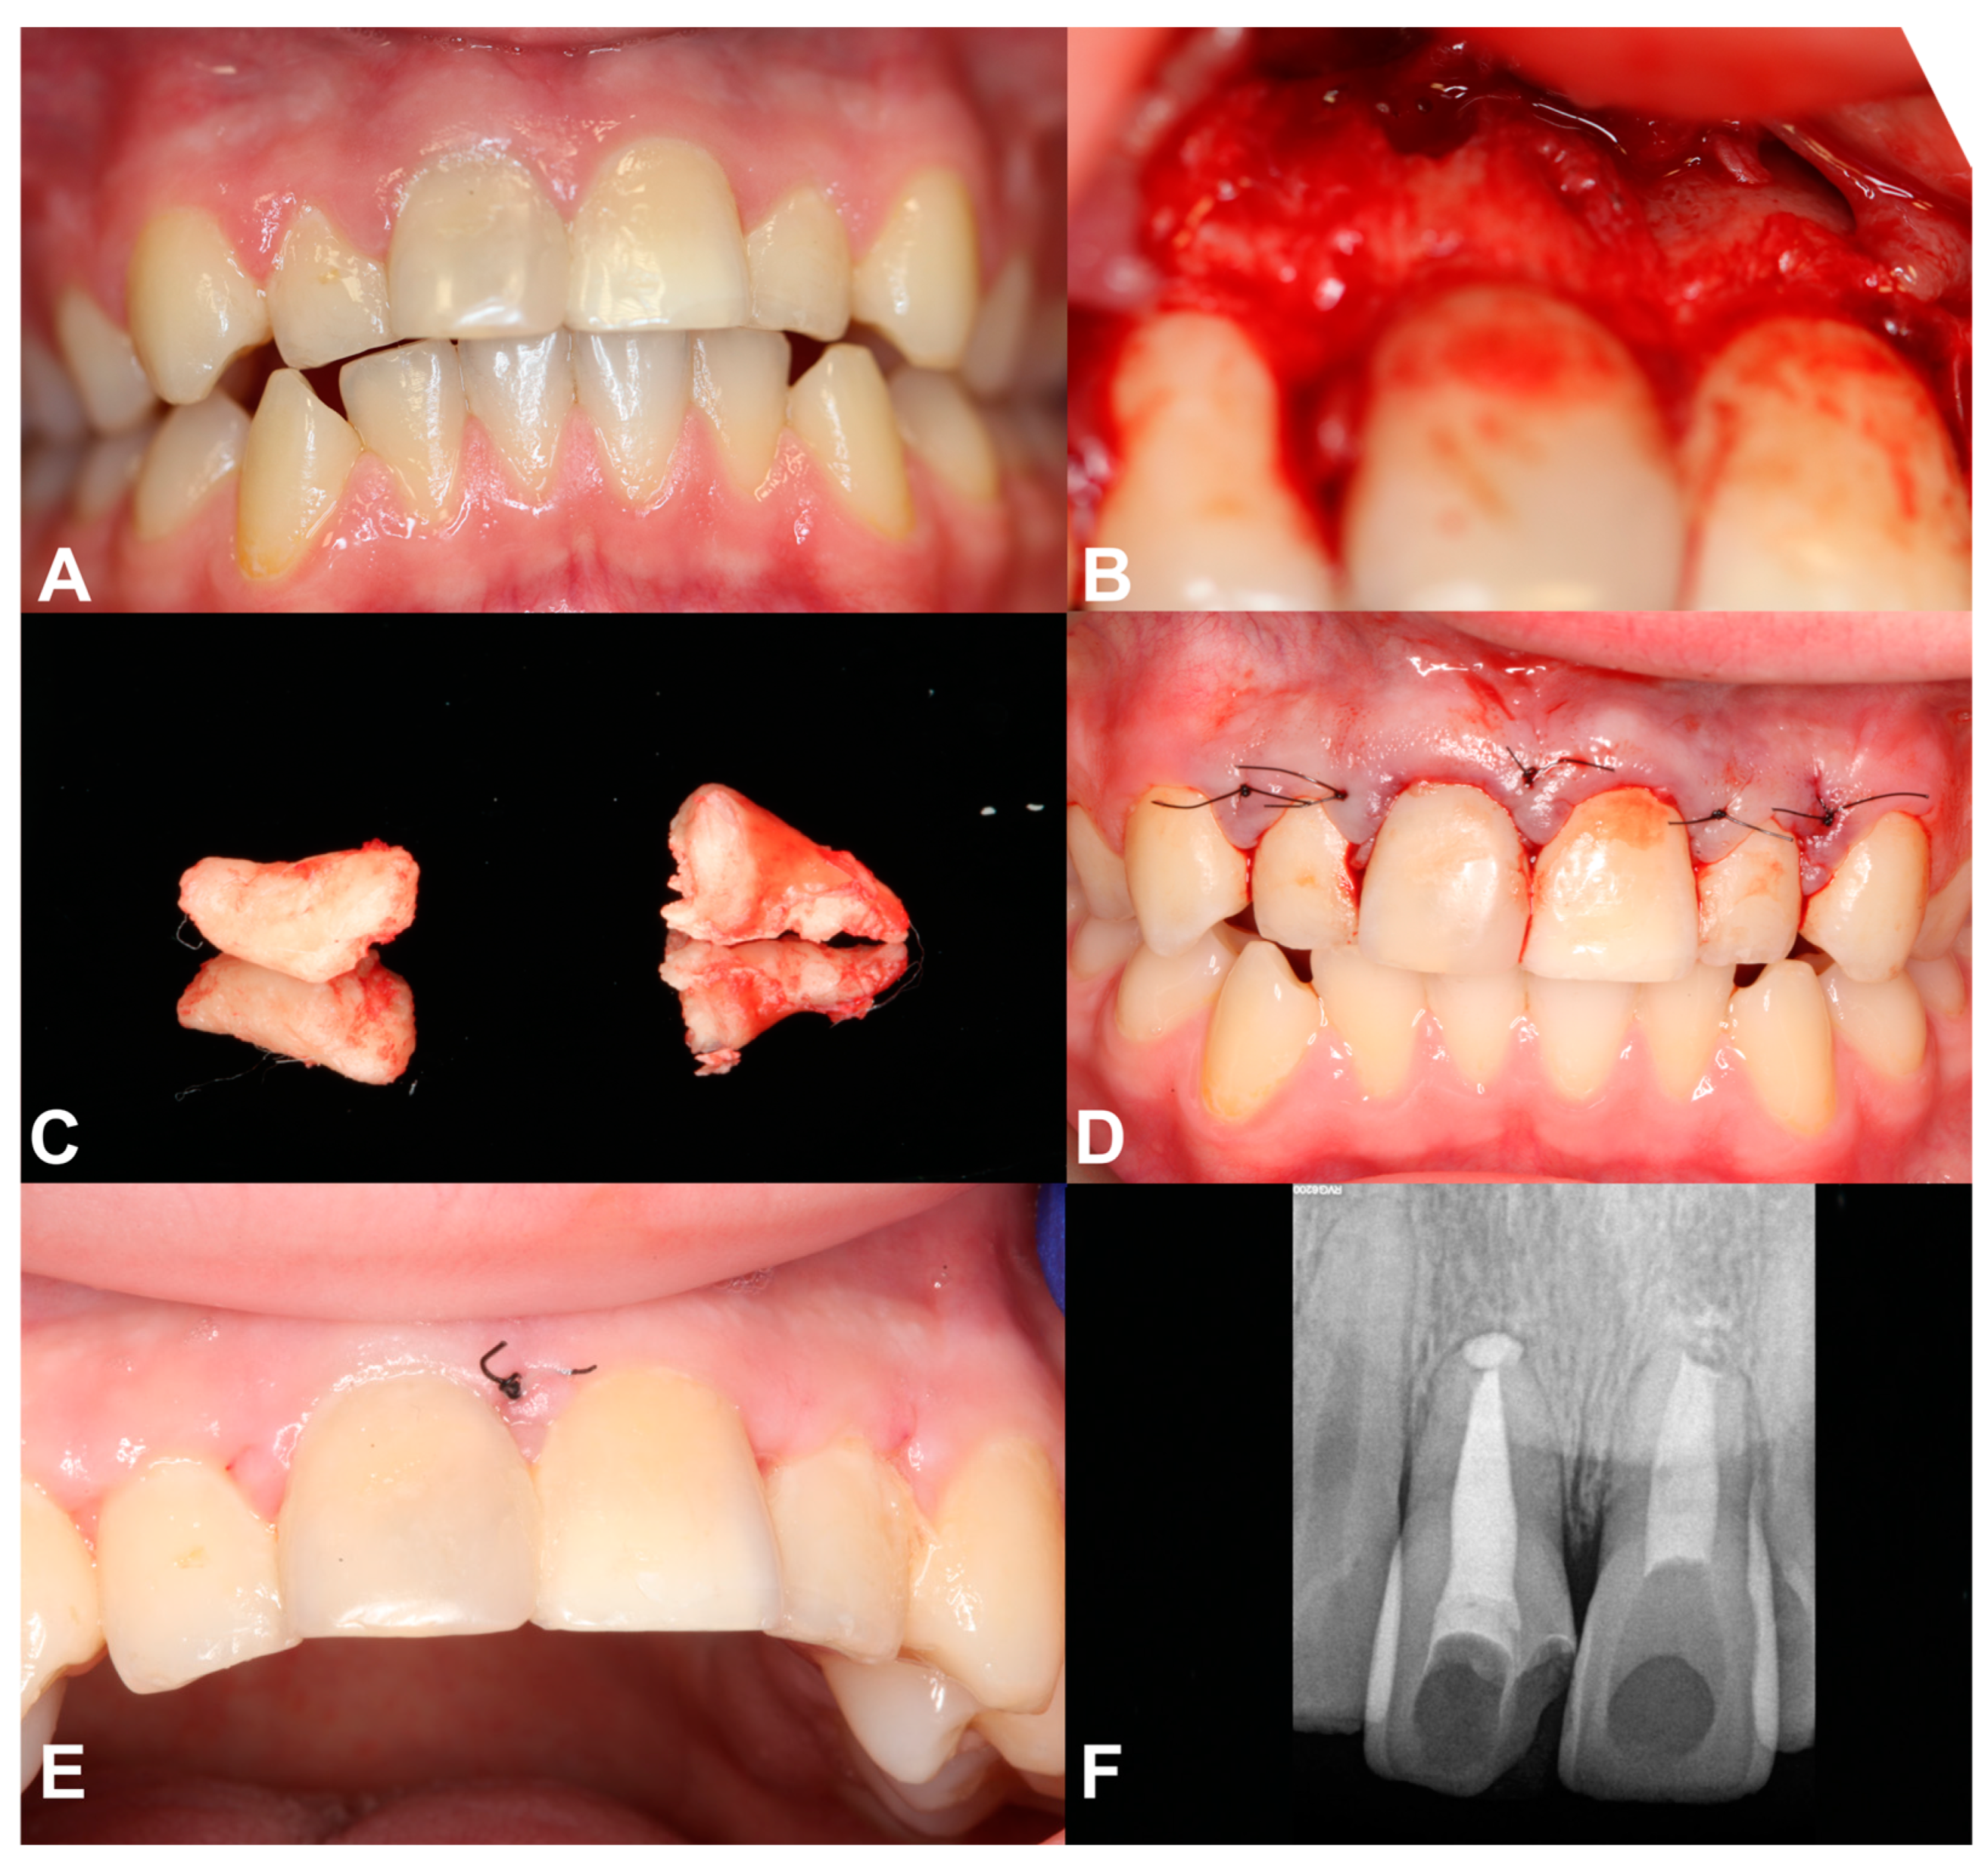

2.3. Case Report 3